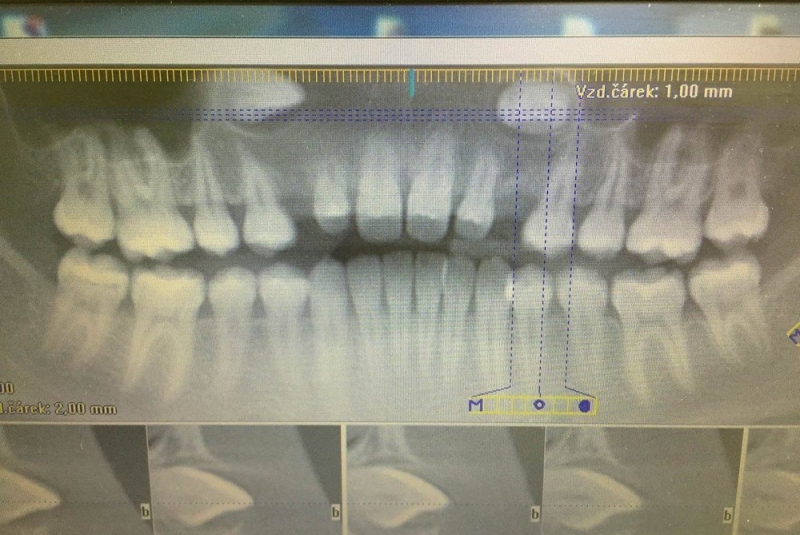

- Implantológia:

1. nadstavba kosti augmentačnými materiálmi (umelé kostné tkanivo, sinus lift a pod.)

2. implantológia, vrátane 3D - dentálneho CT